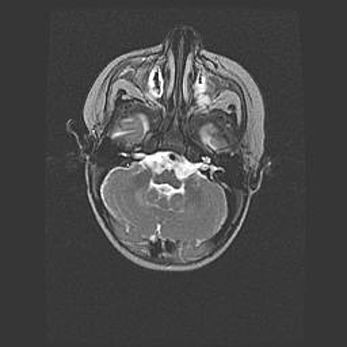

Церебральная ишемия II.

Возраст: 5 дней

Вес: 3400 г

Пол: женский

Окружность головы: 35 см

Срок гестации: 39 недель

Церебральная ишемия – это заболевание, характеризующееся недостаточностью (гипоксией) либо полным прекращением (аноксией) снабжения мозга кислородом по причине закупорки одного или нескольких сосудов. Это приводит к  что метаболическим расстройствам различной степени тяжести в тканях головного мозга, развитию коагуляционных некрозов и гибели нейронов.